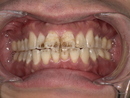

2. Before|来院時の状態(歯石・着色の蓄積)

患者様は長年のコーヒー習慣によって、前歯を中心に強い着色がついている状態でした。とくに目立った特徴は以下の通りです。

●前歯の表面が茶褐色に変色

コーヒーのステインが層のように重なり、歯の白さが完全に失われていました。

●歯と歯の間に黒い汚れが蓄積

すき間に入り込んだ着色は、歯ブラシでは落とせません。

●歯石の付着によるザラつき

舌触りでもザラザラ分かるほど歯石が蓄積しており、早期の対応が必要でした。